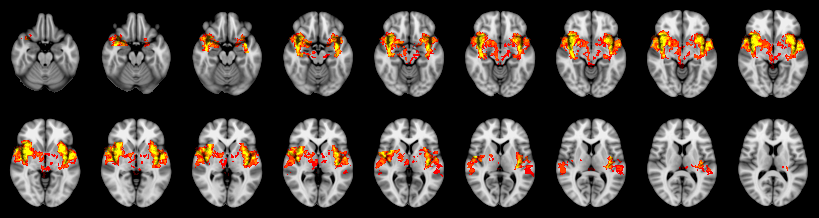

Combined

Mudholkar–George:

Friston:

IUT/Conjunction/Nichols:

Hotelling T2: